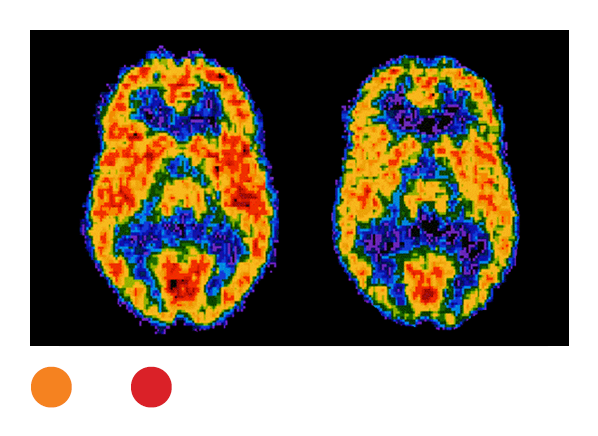

PET

Positron emission tomography requires the patient to ingest a radioactive tracer, usually thru injection, that lands in cells, especially cancer cells. Some machines that are used combine PET and CT scans. Radiation exposure: medium to high.

PET with CT

25

8 years

It exposes patients to very high radiation doses, so make sure that it is really necessary.